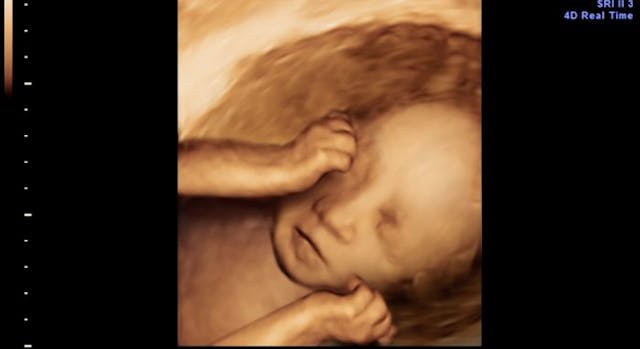

According to reports, she was four and a half weeks beyond the legal abortion age limit in England, which is 24 weeks. That puts her at nearly 29 weeks pregnant when she began seeking out an illegal abortion. Her baby was well beyond the age of viability, and was capable of surviving outside the womb.

Babies born as young as 21 weeks are sometimes able to survive and thrive when given proper medical care.